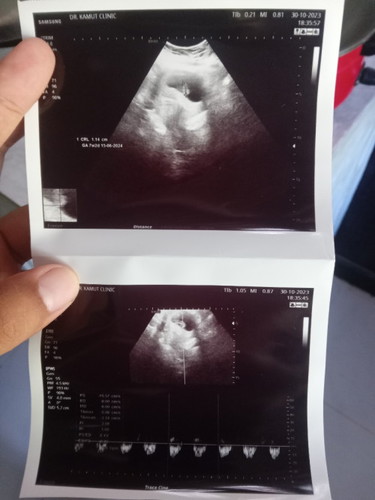

นับปจด.10w ผลซาว7w2d แต่ตอนแม่ท้องแรกไม่เห็นน้องขนาดนี้อันนี้ท้อง2 หรือต้องรอให้น้องโตกว่านี้คะ อายุครรภ์จะชัดกว่านี้ว่ากี่วีค พึ่งซาวด์รอบ2เมื่อวาน ขึ้น7w2dพร้อมเสียงหัวใจเต้นดีมากค่ะ เราต้องยึดอายุครรภ์อันไหนดีคะแม่ๆ